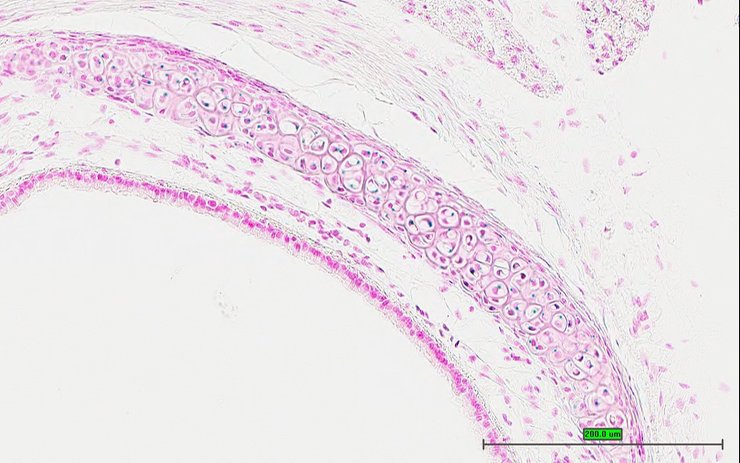

Specimen UC Davis_1888630: postnatal adult; Pms1tm1.1(KOMP)Vlcg/Pms1+ (more )

Structure Level Pattern Image Note

TS28: eye Present UC Davis_1888630

Specimen UC Davis_1888631: postnatal adult; Pms1tm1.1(KOMP)Vlcg/Pms1+ (more )

TS28: eye Present UC Davis_1888631